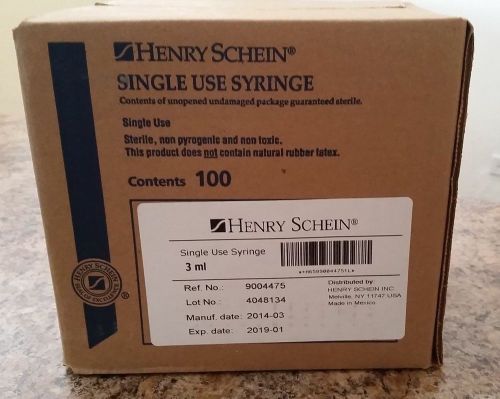

3ml Disposable Syringe 3cc LL (Luer Lok) HSI w/o Needle Sterile 100/Bx